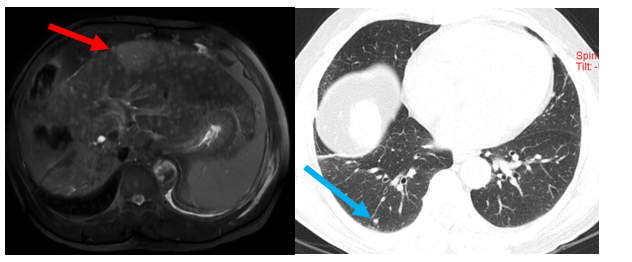

Hình 1: Hình ảnh chụp cộng hưởng từ ổ bụng tháng 8/2020: Hình ảnh hai nốt khu trú kích thước 35x36mm và 14x15mm, vị trí gan phải tính chất động học HCC (mũi tên đỏ).

Hình 2: Hình ảnh chụp cắt lớp vi tính ổ bụng tháng 1/2021 (bên trái) và tháng 4/2022 (bên phải): Hình ảnh u gan phải sau điều trị kích thước 18x22 mm, còn tăng sinh mạch (mũi tên đỏ). Hình ảnh u gan phải sau điều trị kích thước 18x22 mm, không còn tăng sinh mạch (mũi tên xanh).

Hình 5: Hình ảnh chụp cộng hưởng từ ổ bụng (bên trái) và hình ảnh chụp cắt lớp vi tính ngực (bên phải)  (Tháng 3/2024): Hình ảnh u gan đa ổ ở hạ phân thùy III, khối lớn nhất có kích thước 45x58mm, không rõ tính chất HCC (mũi tên đỏ). Hình ảnh nốt đặc nhỏ thùy dưới phổi phải kích thước 6 mm (mũi tên xanh).